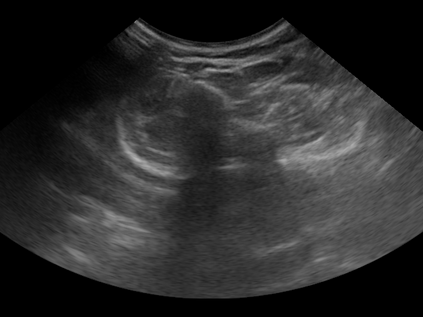

Three-dimensional (3D) freehand ultrasound (US) reconstruction without a tracker can be advantageous over its two-dimensional or tracked counterparts in many clinical applications. In this paper, we propose to estimate 3D spatial transformation between US frames from both past and future 2D images, using feed-forward and recurrent neural networks (RNNs). With the temporally available frames, a further multi-task learning algorithm is proposed to utilise a large number of auxiliary transformation-predicting tasks between them. Using more than 40,000 US frames acquired from 228 scans on 38 forearms of 19 volunteers in a volunteer study, the hold-out test performance is quantified by frame prediction accuracy, volume reconstruction overlap, accumulated tracking error and final drift, based on ground-truth from an optical tracker. The results show the importance of modelling the temporal-spatially correlated input frames as well as output transformations, with further improvement owing to additional past and/or future frames. The best performing model was associated with predicting transformation between moderately-spaced frames, with an interval of less than ten frames at 20 frames per second (fps). Little benefit was observed by adding frames more than one second away from the predicted transformation, with or without LSTM-based RNNs. Interestingly, with the proposed approach, explicit within-sequence loss that encourages consistency in composing transformations or minimises accumulated error may no longer be required. The implementation code and volunteer data will be made publicly available ensuring reproducibility and further research.